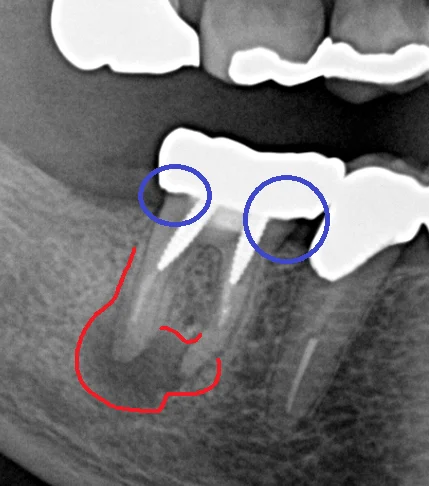

こちらが、初診時のレントゲン写真です。

このレントゲンだけ見ても、分かりづらいと思いますので、少し分かりやすく線を描いたものも載せます。

まず青丸の部分ですが、入っているクラウンの適合があまり良くなく、通常の歯よりも大きく膨らんだ形の被せ物が入っています。 こういった形態の補綴物を入れると被せ物と歯の間が磨きづらく・・・

虫歯になったり歯周病になりやすくなります。

根の方には大きなネジのような土台が2本入っているのですが、非常に歯の壁ギリギリの所に入っているため、この時点で患者さんにはパーフォレーションを起こしてしまっている可能性が高いことを説明しました。

赤丸の所に非常に大きく膿が溜まっています。サイズ的には歯の全長の1/3~1/2程度ですので、歯科医師によっては抜歯を視野に入れる状態かと思います。